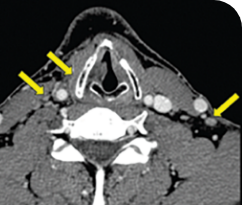

BASELINE

AFTER 31 MONTHS

33-YEAR-OLD MALE4

PATIENT CASE:

METASTATIC, RAIa-REFRACTORY,

PAPILLARY THYROID CANCER1,2

- 33-year-old male

- Progression on RAI and first line systemic therapy

- PRa after 2 cycles of VITRAKVI® (larotrectinib)

- Confirmed partial response on VITRAKVI lasting 55 cycles

Clinical presentation1

- Initially diagnosed at age 27

- Bulky disease in neck and thoracic involvement; metastatic, RAI-refractory papillary thyroid cancer

Prior treatments and outcomes1

- 5 prior surgeries

- 2 prior RAI treatments

- Systemic therapy with pazopanib and trametinib

Testing1,2

- ETV6a-NTRK3a gene fusion was detected during disease progression on systemic therapy via NGS

VITRAKVI treatment1

- VITRAKVI 100 mg twice daily orally

Response to VITRAKVI1,2

- Confirmed partial response (92.6% reduction in target lesions)

- Treatment continued for 55 cycles

- VITRAKVI was well tolerated; patient did not have to discontinue due to AEa

- No treatment interruptions or dose reductions

Response in primary and metastatic lesions1

Images courtesy of Dr Steven Waguespack.